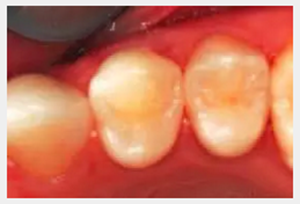

前磨牙復(fù)合樹脂二類修復(fù)